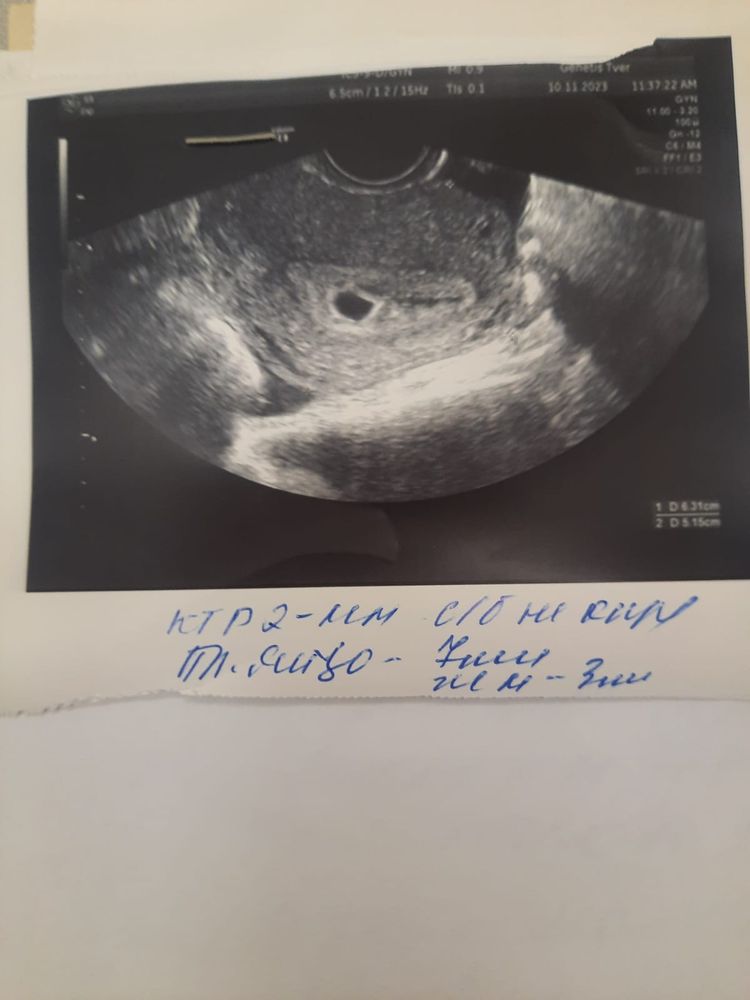

УЗИ 5 недель, гематома

Всем доброго дня✨️Срок по месячным 5.3 нед. Была на первом узи сегодня. ПЯ 7 мм, ктр 2 мм, жм 3 мм. Рядом с ПЯ гематома тонкой полосой. Не кровило. Живот иногда потягивало, но думаю из-за чрезмерной активности (работа, с младшив в сад, уборка, готовка) Подскажите, это гематома так уже затягивается? На узи растерялась не спросила, сейчас себя извожу. Ранее было три замерших, очень волнительно😔